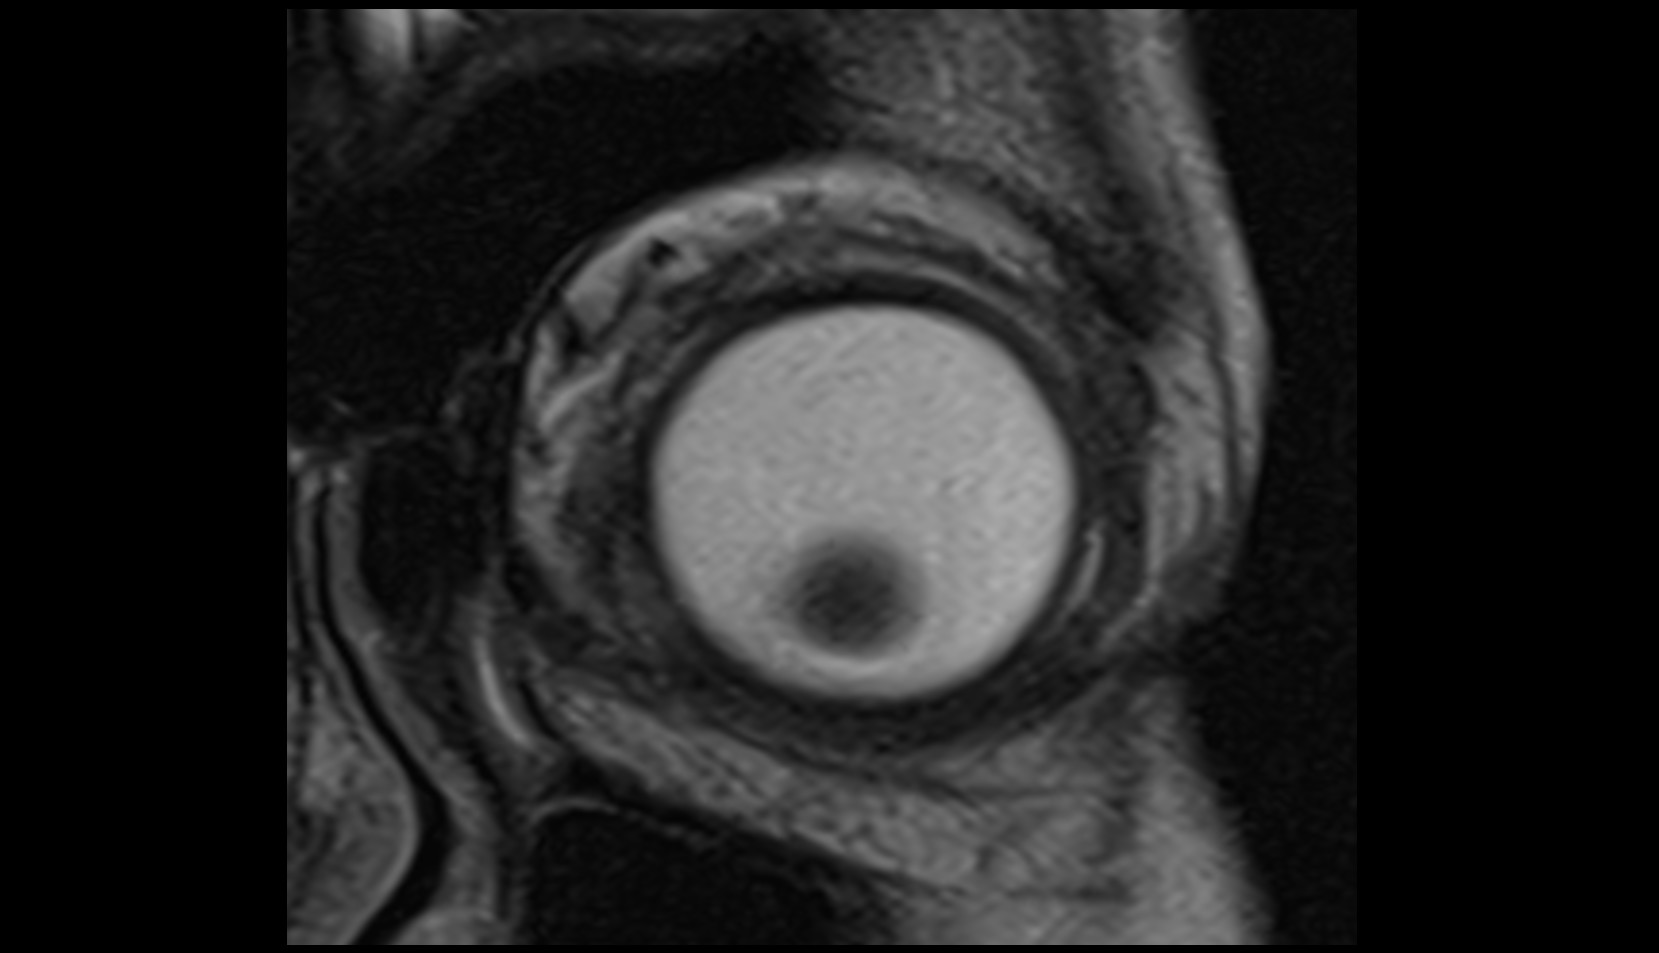

- Peripheral zone of prostate

- Anterior Fibromuscular Stroma of prostate

- Central zone of prostate

- Transitional zone of prostate